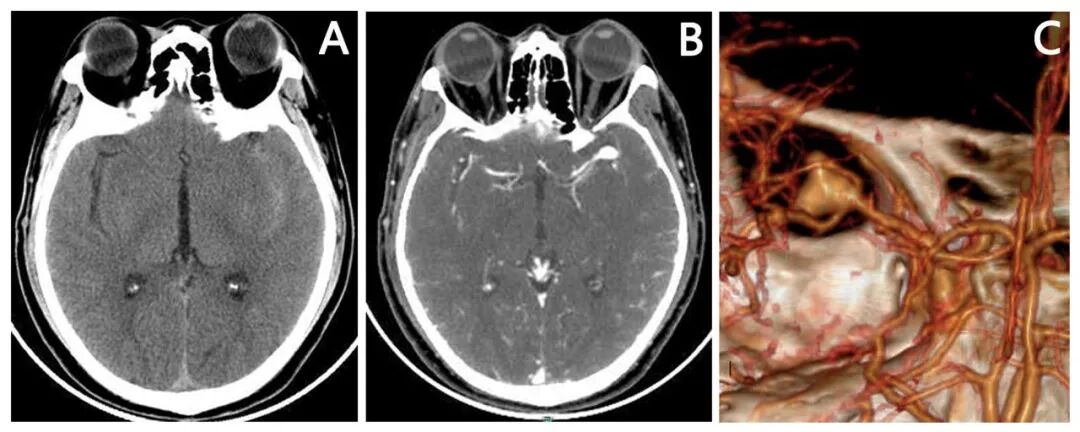

头颅CT平扫:左侧侧裂池及鞍上池蛛网膜下腔出血。(图1A)

头颅CTA:左侧大脑中动脉动脉瘤。(图1B,C)

图1. 患者入院后行头颅CT和CTA检查结果提示左侧大脑中动脉瘤。(A)术前头颅CT平扫提示左侧侧裂池蛛血;(B)术前头颅CTA增强原始片提示左侧侧裂池团状异常高密度影;(C)术前头颅CTA三维重建片提示左侧大脑中动脉分叉部(主干和颞前动脉分叉部)大动脉瘤(约8mm)。

头颅CT平扫:双侧侧裂池,鞍上池,环池,纵裂池蛛网膜下腔出血。(图4A)

头颅CTA:右侧大脑中动脉动脉瘤。(图4B,C)

图4. 患者入院后行头颅CT和CTA检查结果提示右侧大脑中动脉瘤。(A)术前头颅CT平扫提示双侧侧裂池,鞍上池,环池,纵裂池蛛网膜下腔出血;(B)术前头颅CTA增强原始片提示右侧侧裂池团状异常高密度影;(C)术前头颅CTA三维重建片提示右侧大脑中动脉分叉部(主干和颞前动脉分叉部)大动脉瘤(约10mm)。